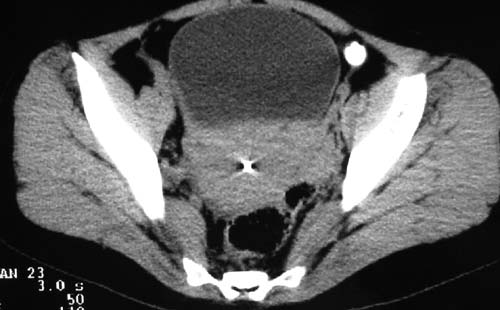

二、男,55岁,排尿困难两年,b超示盆腔不均质包块,ct值约27hu.

第二例可能为脐尿管肿瘤。

例2:盆腔占位,肿块密度欠均匀,其内有钙化影,其边界清晰,膀胱前上壁受压,膀胱壁尚清晰,考虑为不典型畸胎瘤压迫膀胱可能,建议增强扫描吧。

病例1;畸胎瘤,子宫肌瘤。病例2,与膀胱关系密切,脐尿管癌?

2.考虑脐尿管肿瘤

1典型盆腔畸胎瘤.2考虑脐尿管类肿瘤,建议增强扫描.

病例1,盆腔畸胎瘤并子宫肌瘤;病例2,囊性肿块,周围有壳状钙化,膀胱受压改变,考虑:脐尿管囊肿并感染,畸胎瘤?

1盆腔畸胎瘤伴子宫肌瘤2 第二例可能为脐尿管肿瘤。